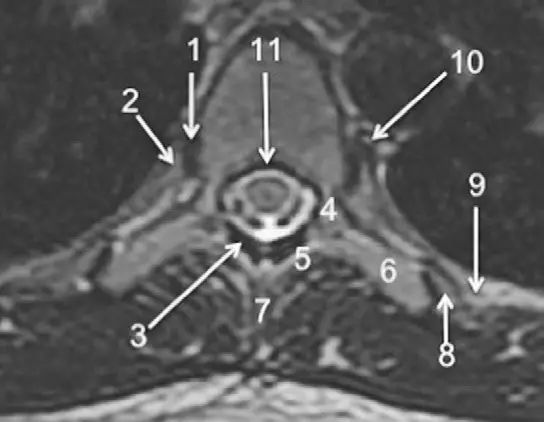

脊柱的MRI解剖